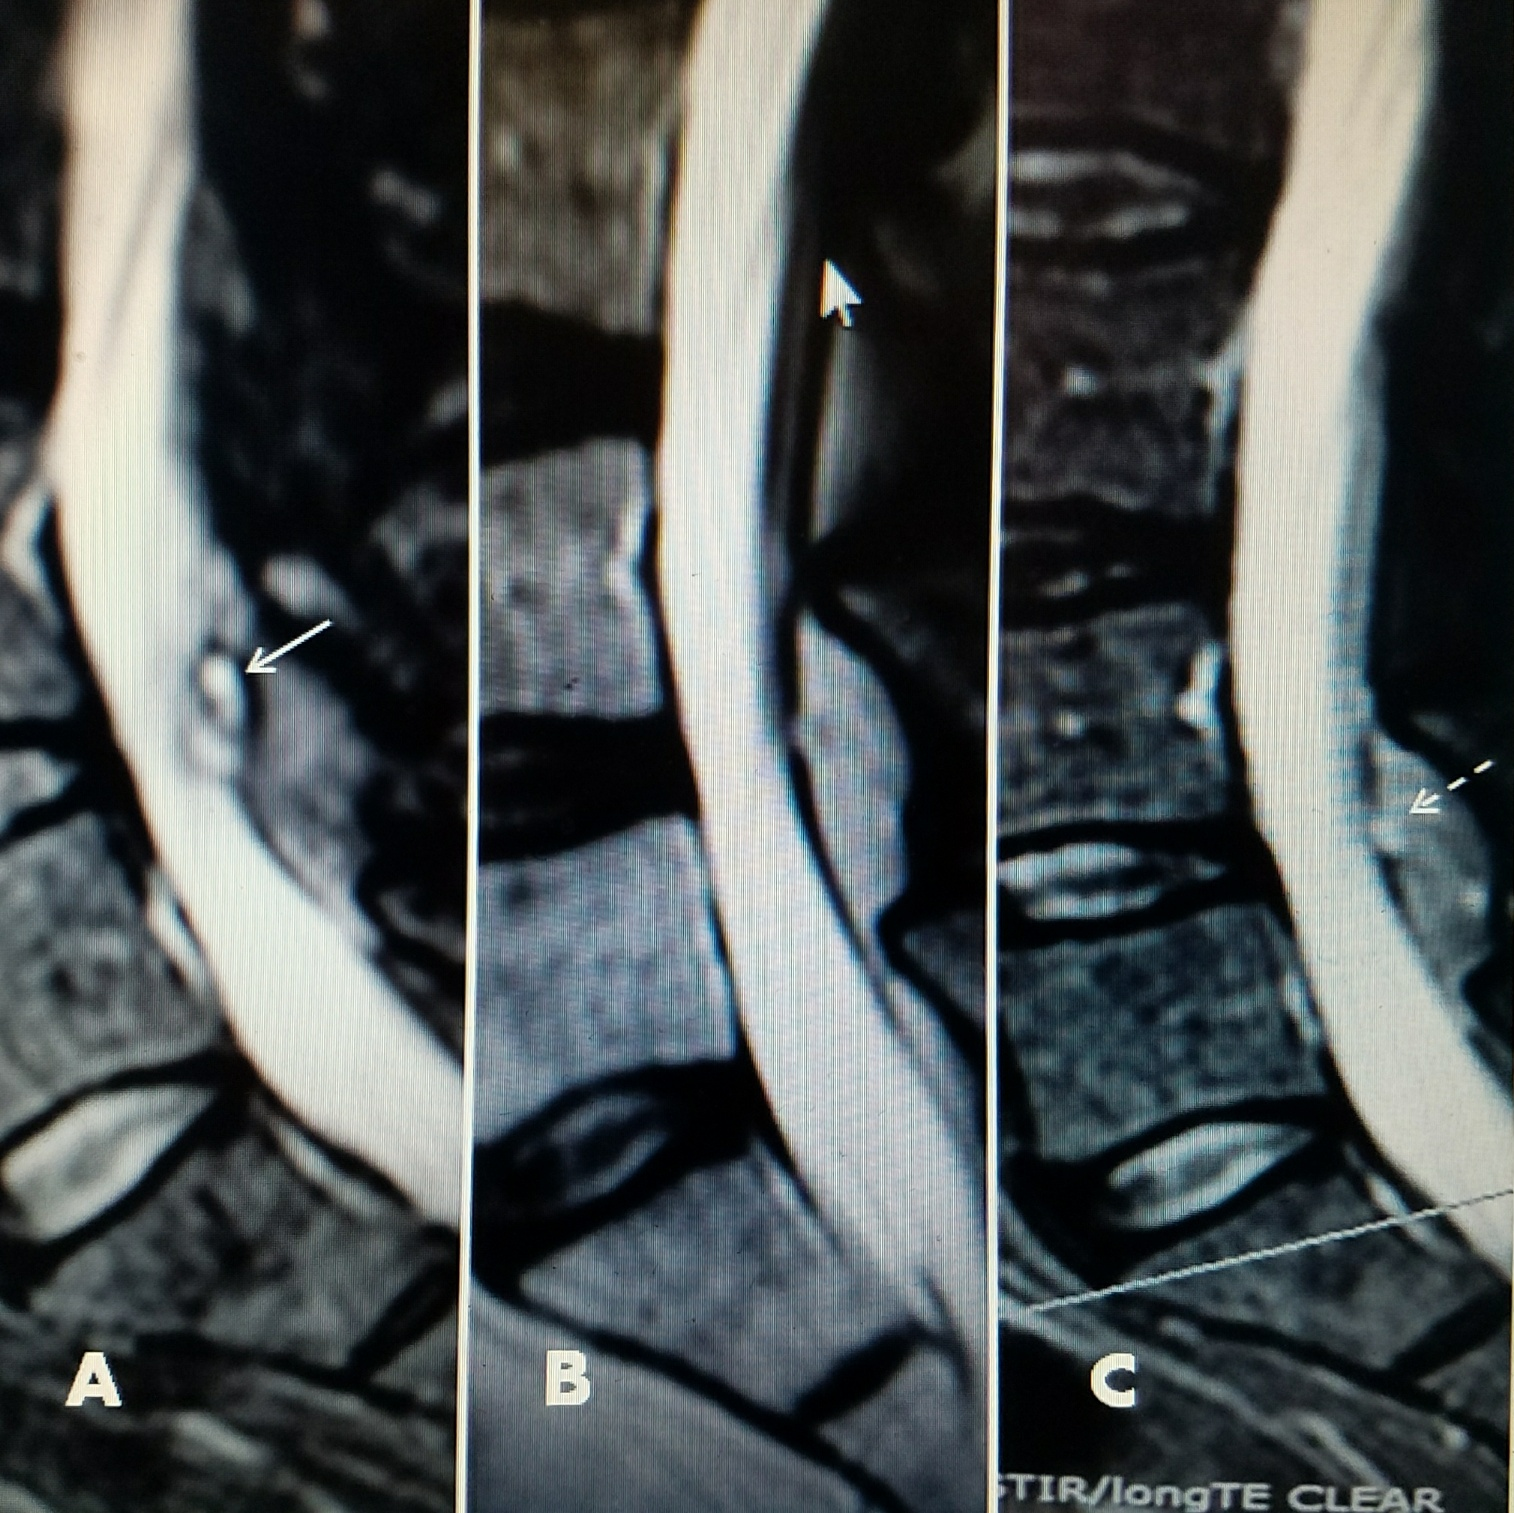

A 79-year-old female with a history of low-grade lumbar pain for three years subsequently developed, over a period of eight months, increasingly severe and constant left leg pain. This was aggravated by extension and left lateral bending, and it was associated with intermittent left leg numbness. There was no relief with a combination of anti-inflammatory medications and physical therapy. An MRI scan showed a left L5-S1 foraminal cyst. She underwent percutaneous drainage and RF ablation of the cyst and left L5-S1 facet capsule. Pre-procedure VAS was 8/10. Post-procedure she had complete relief of her leg pain and return of full spinal motion. In followup after 18 months, she has continued pain-free with VAS score of 0/10 with a full range of motion (Figure 3).